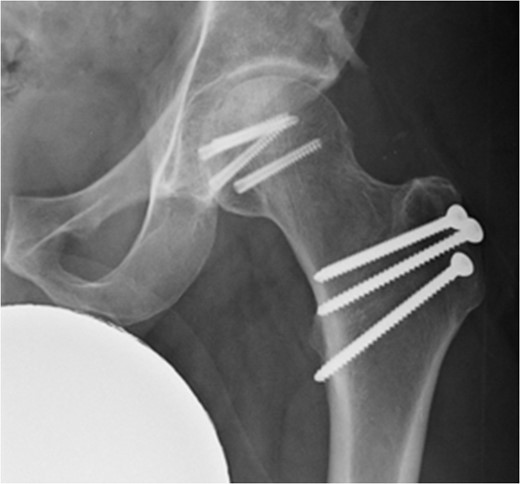

In addition to the bony injury, labral detachment and tearing were noted (later repaired with suture anchors). The femoral head was comminuted and had areas of missing articular cartilage especially posteriorly and superiorly with a 1 × 1 cm2 area of full thickness cartilage loss (Fig. 4). The weight-bearing zone was relatively unaffected. The ligamentum teres had to be released to allow fracture reduction and fixation with four headless compression screws (Fig. 5). A good fixation was achieved. Microfracture was performed on the articular cartilage defect. The femoral head, fracture fragment and microfracture site were bleeding and appeared viable.

Intraoperative view of the femoral head after fixation with headless compression screws.

At 14 months postoperative, the patient is pleased with his progress. There is no radiographic evidence of avascular necrosis at this stage (Figs 6 and 7). He regularly participates in activities such as cycling, and scores well on the modified Harris Hip Score (81/100), non-arthritic hip score (92.5/100) and SF-12 (41/48).